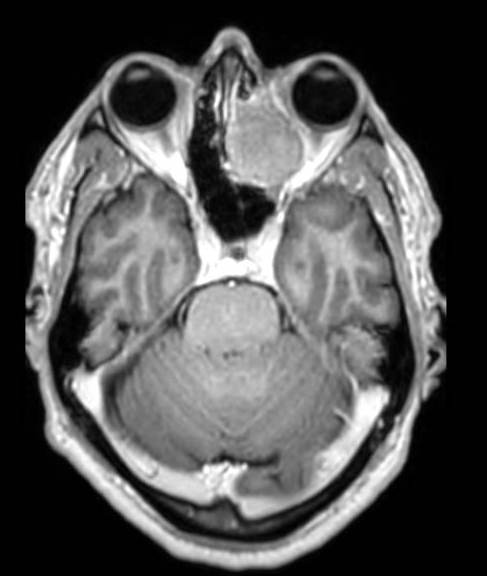

The attached OCT compares 24 (worse) and 28 July (slightly better).

• Optic disc edema improving post-IV steroids (see attached images)

Macular OCT: is there seeping of fluid under the macula causing this worsening in vision?